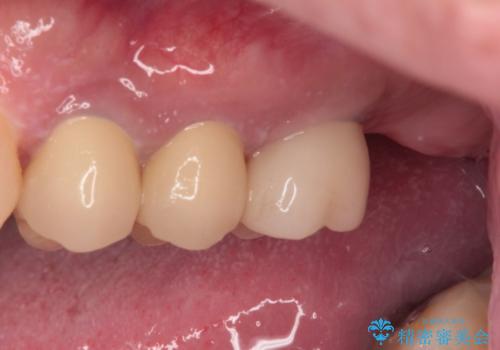

根管治療を行ったままの奥歯 オールセラミッククラウンによる補綴治療

- 以前根管治療を行い、クラウンにする必要があると言われたものの、そのままに放置してしまったとのことで来院された患者様です。

根管治療を行った歯には特に症状がないため、速やかにオールセラミッククラウンにて補綴治療を行うこととしました。

補綴治療前は食後はいつもものが挟まっていたそうですが、補綴治療後はものが挟まる悩みから解放されたとのことでした。